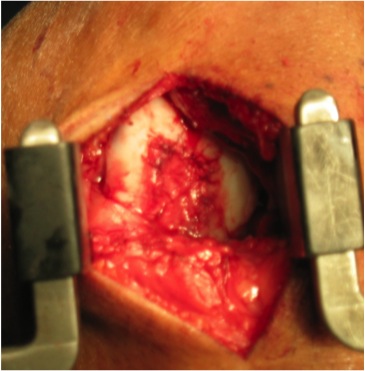

Implantation

- medial or lateral parapatellar approach

- create sharp stable margins

- curette base

- control bleeding with adrenalin soaked gauze to avoid graft displacement

- size defect with foil - graft cannot be prominent or will displace with ROM

- secure with fibrin glue / Tisseal

- ensure graft stability with knee range of motion